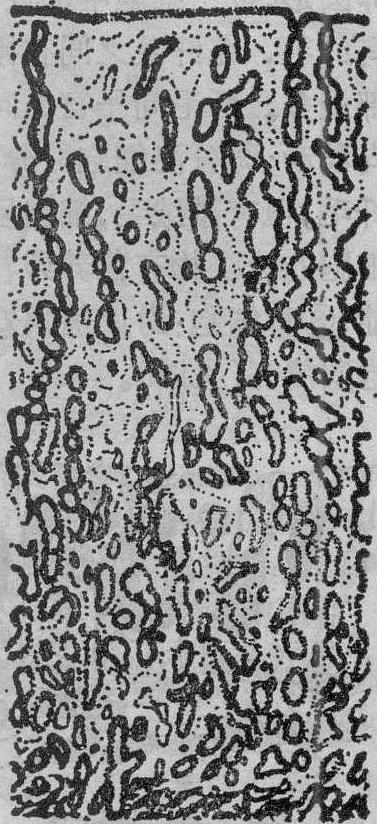

分泌晚期 相当于经前期,约在月经周期第24~28天。内膜增厚达5~10mm,分层较清楚。腺体高度扩张并极度弯曲,腔内充满含糖原的分泌物(图3)。腺上皮细胞高低不一,细胞游离端边缘模糊不清,分泌功能达到高峰。细胞内含有大的高尔基复合体,内质网和很多小线粒体,并有糖原散在。核仁管系统和巨大线粒体消失。螺旋动脉增生,螺旋程度增加,扩张的毛细血管在内膜表面形成小血窦。致密层基质细胞分化成两种形态,一种较肥大,胞质丰富,核呈网状,称为蜕膜样细胞; 另一种小而圆,核分叶,胞质内含分泌颗粒,称为内膜颗粒细胞,其颗粒的成分与松弛素相似,能分解内膜中的网状纤维。在孕激素的作用下,蜕膜样细胞先在螺旋动脉周围积聚,然后逐渐形成一层发育良好的前蜕膜细胞。到分泌晚期的最后2~3天,卵巢中黄体退化萎缩,激素减少。致密层中出现白细胞浸润,海绵层内腺体衰竭,腔内分泌物减少。腺上皮细胞变低,核圆而深染,胞质内RNA消失。

图3 子宫内膜分泌晚期(月经周期第25天)